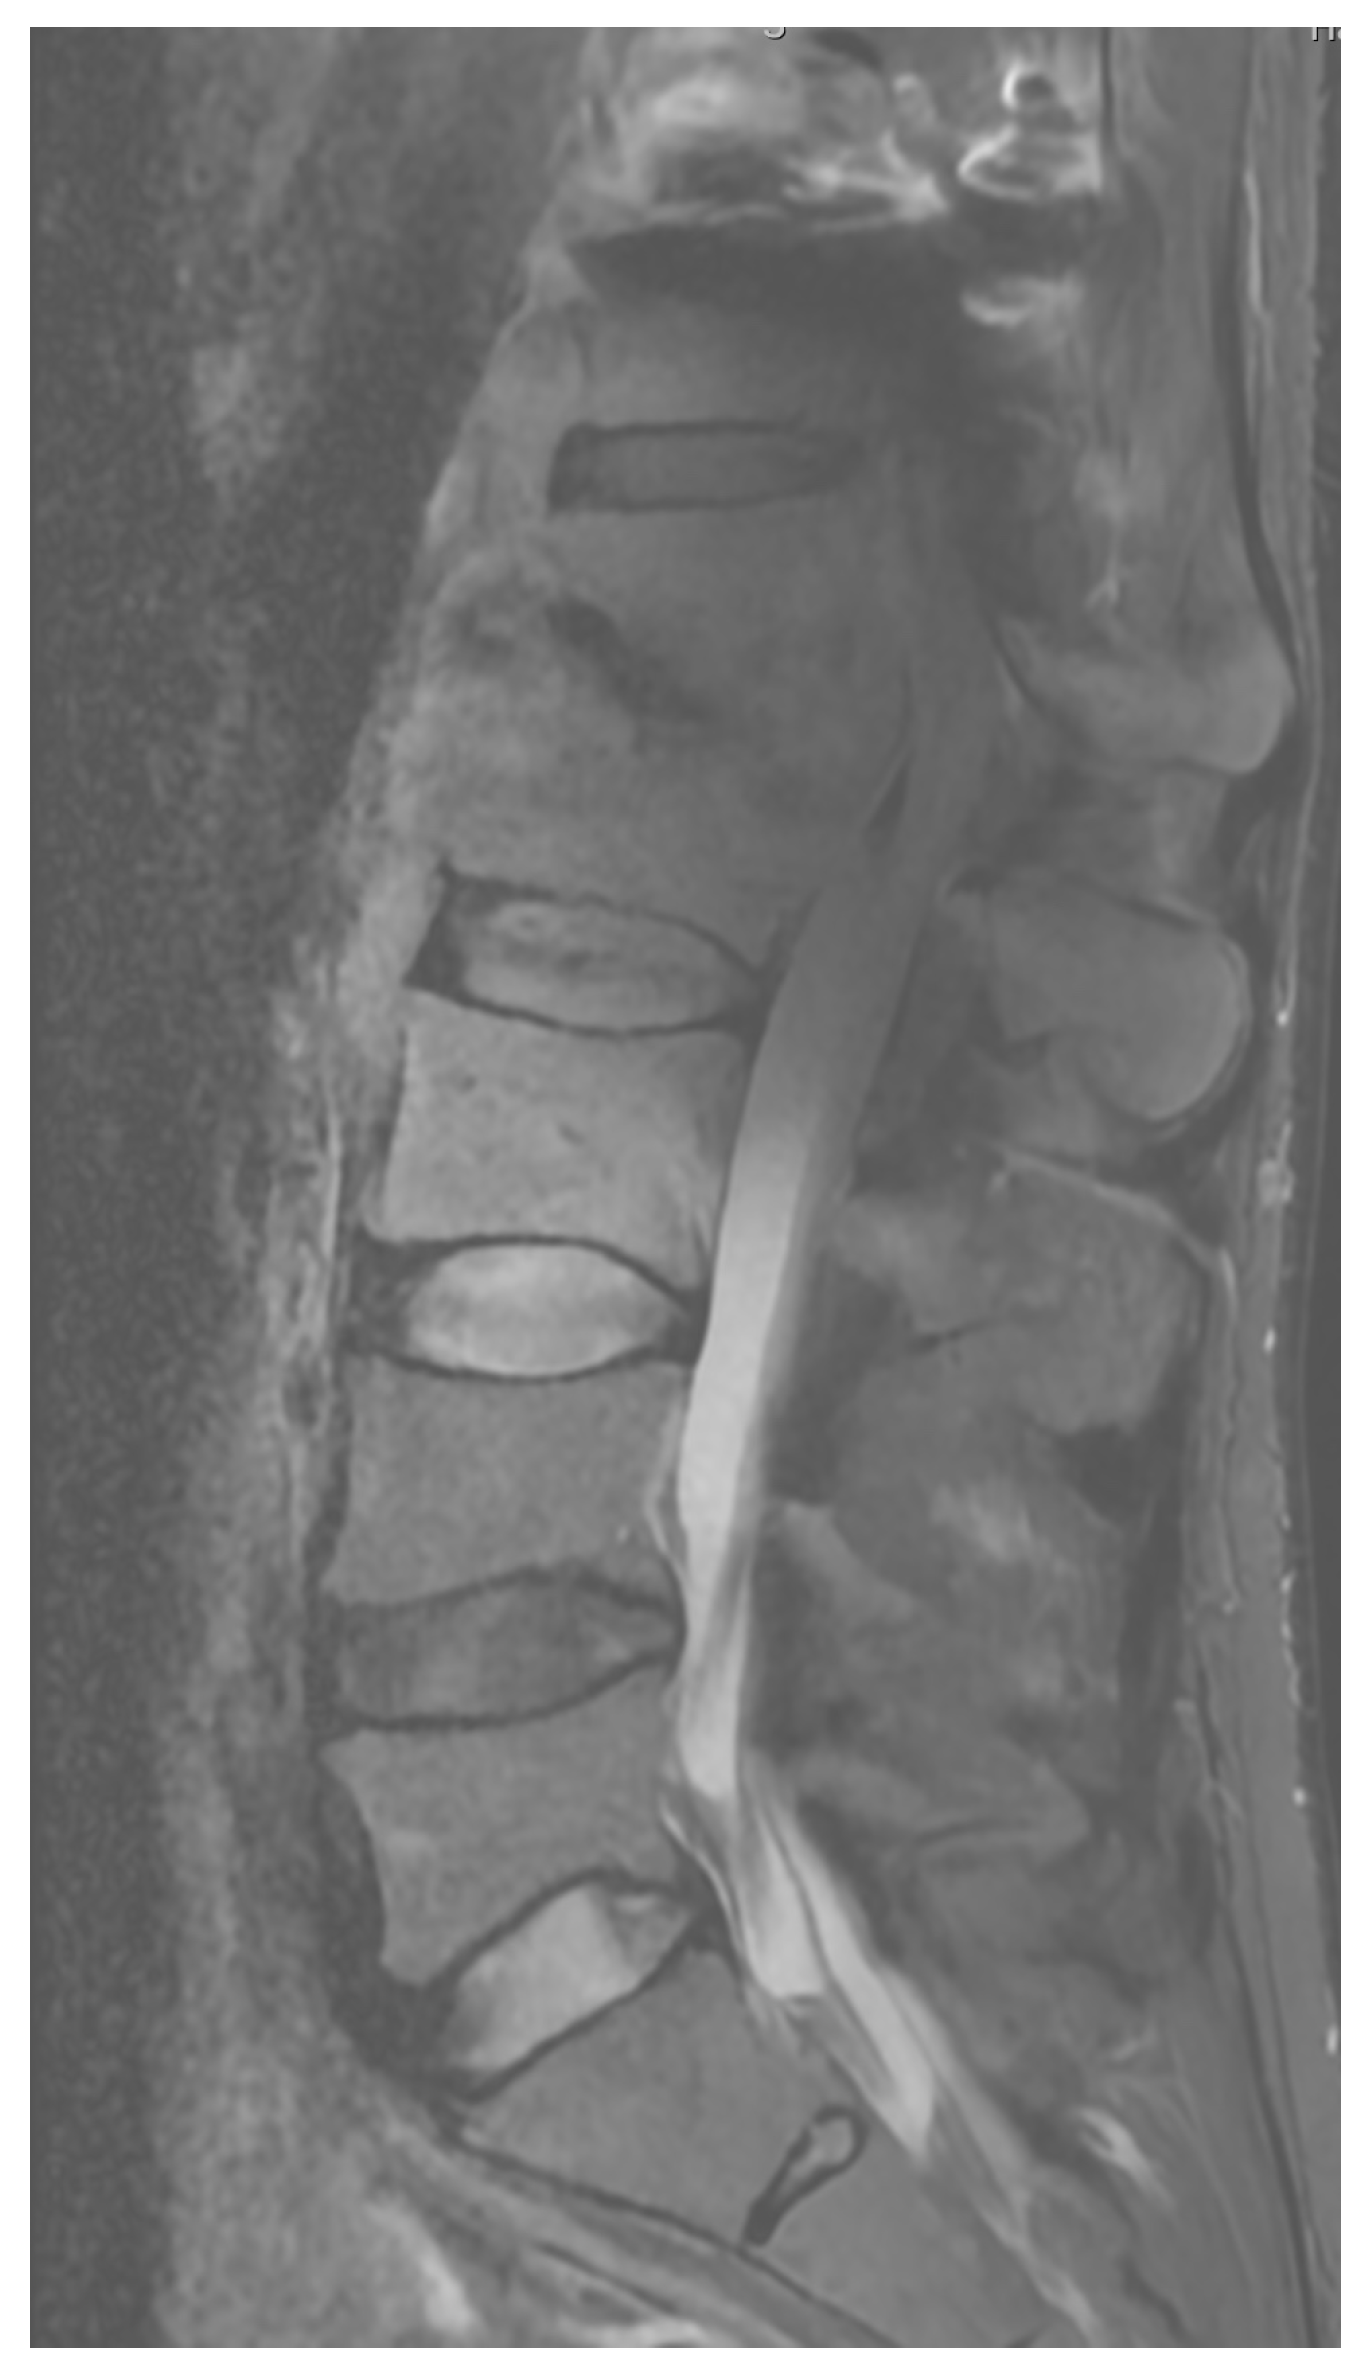

Diagnostic Evaluation: Cultures taken were sterile, and the patient was empirically treated with antibiotics until inflammatory markers decreased. He was discharged in good condition without pain. Six months later, the surgical site re-opened with purulent discharge seeping out. A new culture was taken, which returned sterile. Laboratory tests showed an increase in inflammatory markers, and the patient periodically experienced fever. CT scans showed the stabilization was in the correct position but without signs of bone fusion, and MR images showed inflammatory masses within the spinal canal (Figure 9 and Figure 10).

Figure 10. Pre-operative T2 sagittal MRI.